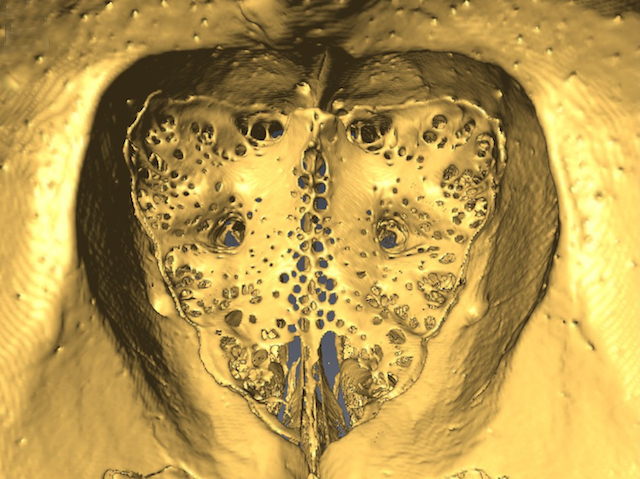

Following Your Nose

Damage to olfactory nerves affects flow of cerebrospinal fluid

Your nose can detect around a trillion smells, in part thanks to its olfactory sensory nerves. These nerves are also involved in clearing out waste that your brain produces, acting as a conduit for the drainage of waste-laden cerebrospinal fluid (CSF). Using mice, researchers dig deeper into the anatomy of CSF removal, focusing on the bone that separates the nasal cavity from the brain, the cribriform plate (pictured, captured using micro-CT imaging). They injected a dye into the brain to track the drainage of CSF via olfactory sensory nerves passing through holes in the cribriform plate. Chemically destroying these nerves significantly reduced CSF drainage via the cribriform plate without increasing pressure inside the skull. This suggests a compensatory change in CSF production or flow. Damage to these nerves in humans, such as by air pollution, could therefore disrupt CSF turnover, which is known to occur in certain brain diseases.